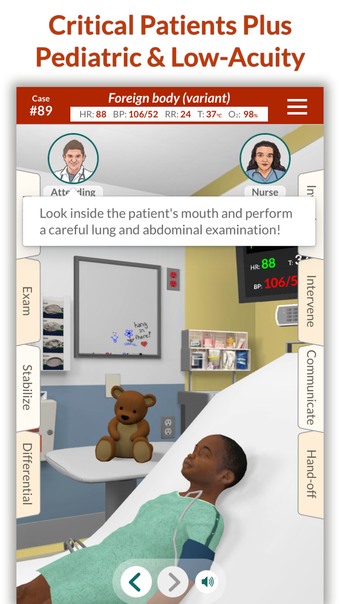

Full Code - Emergency Medicine Simulation è un'applicazione Android sviluppata da Minerva Medical Simulation Inc. È una versione completa con licenza di un'applicazione di stile di vita che rientra nella sottocategoria medica. È un'applicazione di simulazione intuitiva, mobile-first che offre oltre 160 casi virtuali realistici e un'interfaccia coinvolgente simile a un gioco, preferita dai professionisti medici di tutto il mondo. L'applicazione è progettata per aiutare gli studenti e i professionisti medici a acquisire fiducia nel trattamento di casi complessi e offre 0,5 crediti AMA PRA Categoria 1™ per ogni caso Full Code giocato con Full Code Pro+CME.

L'applicazione consente agli utenti di esercitarsi in diagnosi cliniche rare e rischiose in un ambiente sicuro in modo da poter affrontare casi complessi del mondo reale con fiducia. Con oltre 160 casi in 31 specialità, Full Code consente di esercitarsi in simulazioni mediche on-demand ogni volta che si ha una pausa, ovunque ci si trovi. L'applicazione è ottimizzata per la portabilità e l'accessibilità ed è disponibile su qualsiasi dispositivo mobile, desktop o tablet. Full Code è accreditato attraverso l'ACCME e, con la sua sottoscrizione PRO+CME, gli utenti possono completare i loro requisiti di formazione medica continua (CME) con sfide di simulazione flessibili e piacevoli. È un'applicazione eccellente per i professionisti medici che vogliono migliorare le proprie competenze e acquisire fiducia nel gestire casi complessi.